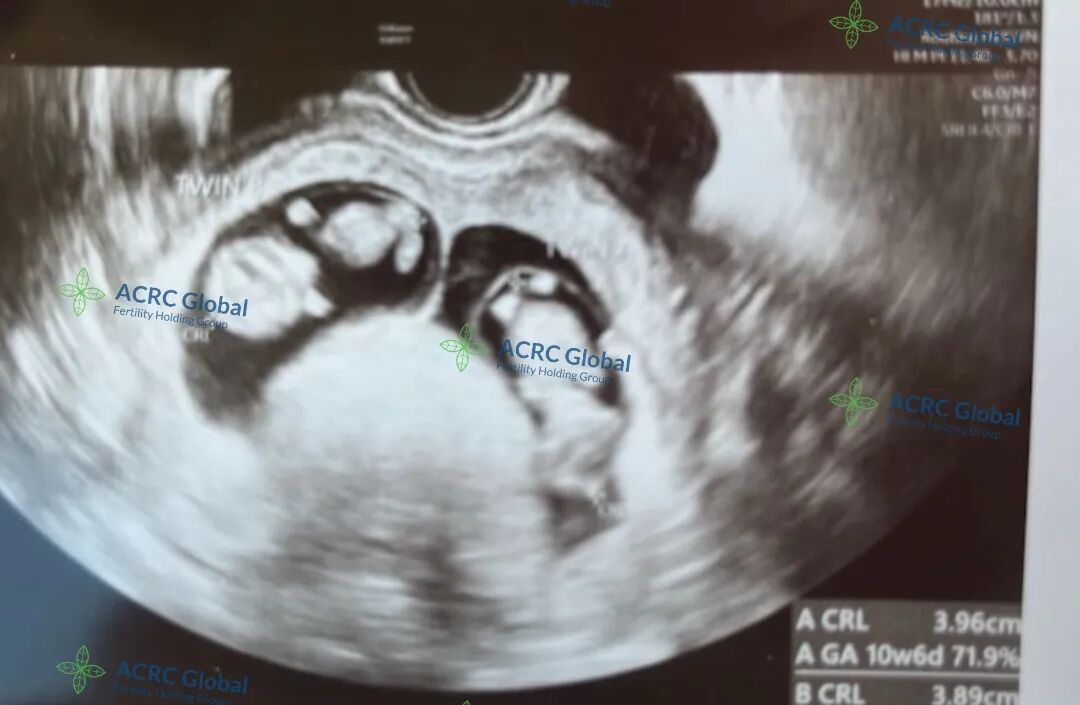

爱妈B的双胎宝宝健康成长中!宝宝们目前已有十周零六天大。我们准父母这次在捐卵女生的帮助下,成功培育出高品质的胚胎,两个宝宝均顺利着床。爱妈B将转至当地妇科诊所继续监控宝宝们的健康发展。